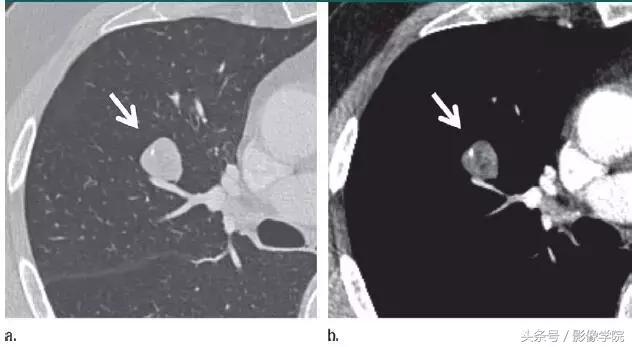

1、错构瘤

图 1 层厚 1 mm 的 CT 横断面图像,(a)为肺窗,(b)为软组织窗,显示边缘平滑、内含脂肪和钙化的实性结节(箭头),符合错构瘤表现。不建议进一步 CT 随访。